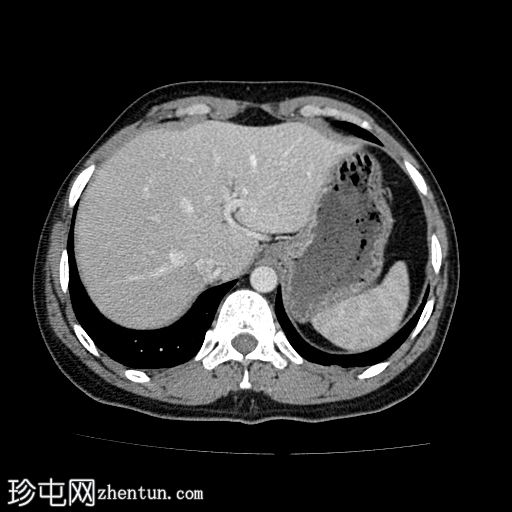

轴位增强扫描(门静脉期)

颈段食管内可见一线状水平方向的高密度异物。

颈段和上胸段食管可见长段环周强化壁增厚,符合异物嵌顿引起的反应性水肿改变。

可见食管壁撕裂,可能与异物的方向有关。此外,可见多个食管周围气腔,提示可能存在食管穿孔。

未见纵隔积气、食管周围脓肿或明显穿孔的证据。